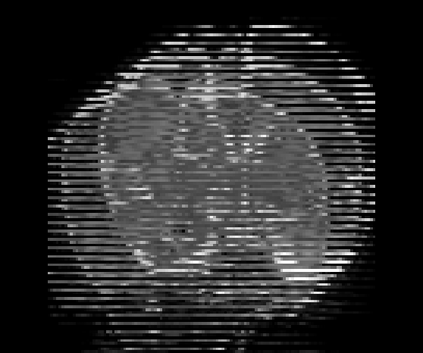

Real-world settings often do not allow acquisition of high-resolution volumetric images for accurate morphological assessment and diagnostic. In clinical practice it is frequently common to acquire only sparse data (e.g. individual slices) for initial diagnostic decision making. Thereby, physicians rely on their prior knowledge (or mental maps) of the human anatomy to extrapolate the underlying 3D information. Accurate mental maps require years of anatomy training, which in the first instance relies on normative learning, i.e. excluding pathology. In this paper, we leverage Bayesian Deep Learning and environment mapping to generate full volumetric anatomy representations from none to a small, sparse set of slices. We evaluate proof of concept implementations based on Generative Query Networks (GQN) and Conditional BRUNO using abdominal CT and brain MRI as well as in a clinical application involving sparse, motion-corrupted MR acquisition for fetal imaging. Our approach allows to reconstruct 3D volumes from 1 to 4 tomographic slices, with a SSIM of 0.7+ and cross-correlation of 0.8+ compared to the 3D ground truth.

翻译:现实世界环境往往不允许获取高分辨率的体积成像,以进行准确的形态评估和诊断;在临床实践中,通常常见的做法是只获得稀少的数据(如个别切片),以进行初步诊断决策;因此,医生依靠其人类解剖学的先前知识(或精神图)来推断基本的3D信息;准确的精神图需要多年的解剖培训,而这种培训首先依靠的是规范学习,即排除病理学;在本文中,我们利用贝耶斯深深层和环境绘图,从零到小、稀少的切片,产生完整的体积解剖面表(如个别切片);我们评估概念实施的证据,其基础是基因质断网(GQN)和致感性BRUNO,使用腹膜CT和大脑MRI,以及临床应用,包括稀疏、运动-腐蚀MRM,用于胎儿成像。我们的方法允许将3D卷从1到4个成像片,用0.7+的SISIM和0.8+的地面与3C的交叉联系。